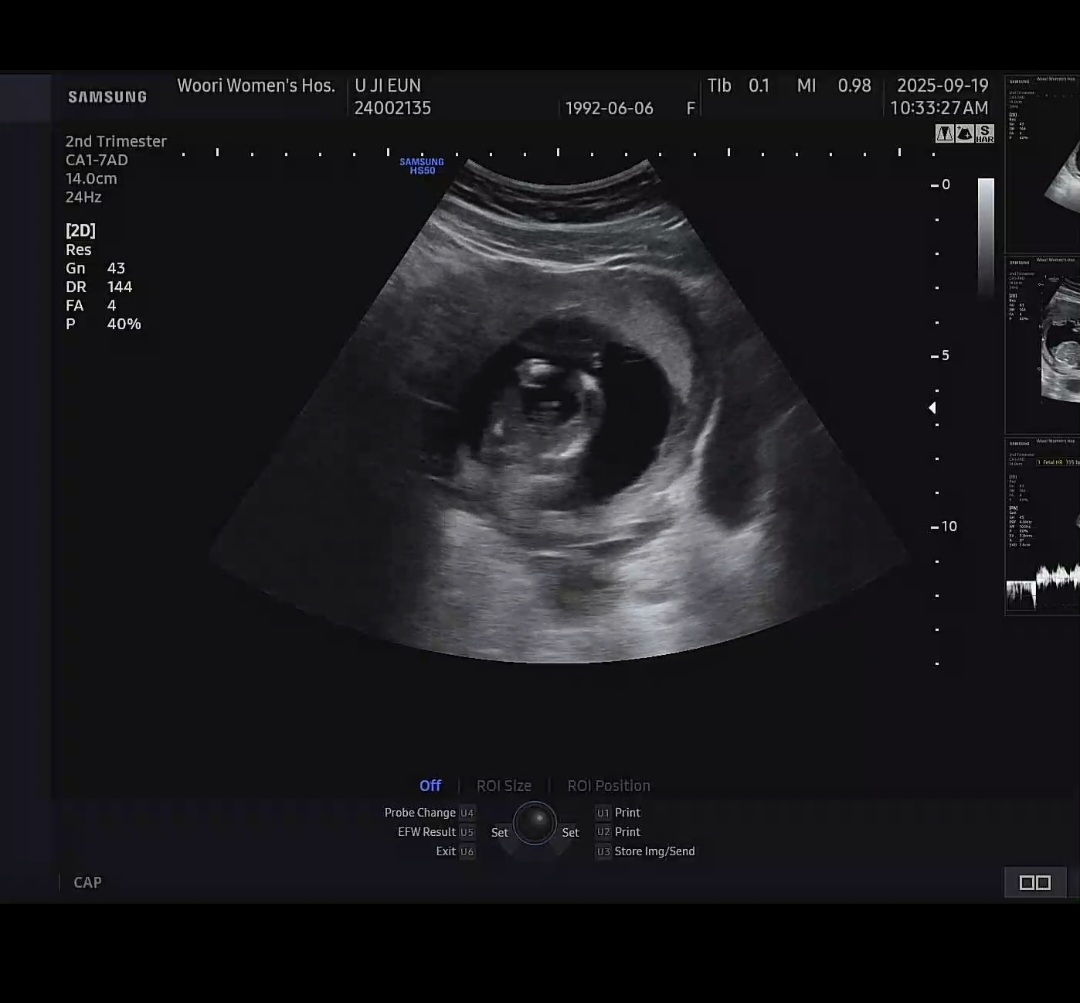

성별 봐주세요🥰

오늘 16주1일차 초음파 보고왔는데.. 다리사이에 탯줄이 있어서 의사선생님은 긴가민가 하다고 하시더라구요 ㅠㅠ 뭔가 보이는거 같기도하고 하시면서.. 오늘 초음파 사진인데 같이 봐주세요!!